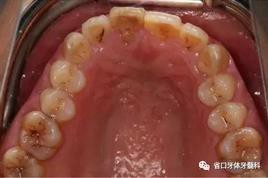

1.?病例簡(jiǎn)介 43歲女性患者,主拆:右上前牙松動(dòng)不適數(shù)日要求修復(fù)。現(xiàn)病史:患者數(shù)年前右上前牙因“齲壞”于外院行根管治療(具體不詳),數(shù)日前牙冠松動(dòng)不適,現(xiàn)覺(jué)影響咀嚼及美觀,遂來(lái)我院要求進(jìn)一步診治。否認(rèn)高血壓、心臟病等重大疾病,否認(rèn)結(jié)核、肝炎等傳染病史,否認(rèn)手 術(shù)、輸血史等,未發(fā)現(xiàn)藥物過(guò)敏。無(wú)吸煙習(xí)慣。臨床檢查:口外觀顏面基 本對(duì)稱,皮膚無(wú)紅腫破潰,顳下頜關(guān)節(jié)區(qū)無(wú)彈響、雜音、壓痛,開(kāi)口度約 37mm,開(kāi)口型“↓”,頜下、刻下和頸部未及腫大淋巴結(jié)。中位笑線??趦?nèi)檢查,口腔衛(wèi)生可,色素(+),BOP(-),PD=2mm,上頜右側(cè)中切 牙冠部變色,冠根折斷至齦下3mm,叩不適,松動(dòng)Ⅱ°~Ⅲ°。牙齦稍紅, 齦緣水平及齦乳頭高度可,屬于中厚齦生物型,附著齦寬度約5mm,唇系帶附著可。上頜右側(cè)中切牙缺牙間隙與對(duì)側(cè)同名牙一致,約>7mm,修復(fù)空 間良好。與對(duì)頜牙覆合覆蓋正常。MCT檢查示上頜右側(cè)中切牙冠根折斷至骨 下,根管內(nèi)見(jiàn)充填物,根充不全,根尖見(jiàn)陰影,大小約3mm×3mm。牙槽窩根方可用骨量可,唇側(cè)骨壁完整,冠方骨壁厚度約1mm。

圖1 術(shù)前口內(nèi)照

圖2 術(shù)前口內(nèi)照

圖3 術(shù)前口內(nèi)照